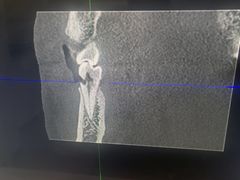

• Dr.Z dental仁康种植矫正中心

• -Dr.Z dental仁康种植矫正中心

糊涂印象 | 23-01-10